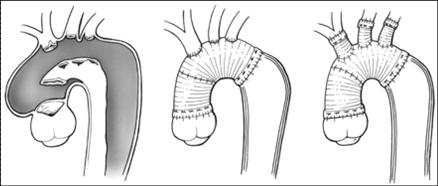

Yapay damarla aort diseksiyonu tamiri. Bu tür ameliyatlarda kalp akciğer makinesi kullanılarak hastanın vücut sıcaklığı 19?C’ye kadar soğutulmakta ve ameliyat bitinceye kadar dolaşım tamamen durdurulabilmektedir.